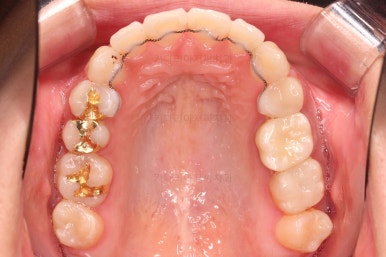

어느새 틈도 다 닫히고요.

마무리 과정만 남았습니다.

4. 마무리

틈이 다 없어졌고, 교합도 양호합니다.

무엇보다 임플란트 없이 결손부위가 깔끔하게 채워졌고요.

매우 다행으로 사랑니도 다 있었기 때문에 마치 큰 어금니가 다 있는 것과 같은 상황이 되었습니다.

역설적이게도 손상된 큰 어금니가 없었던 부위는 작은 어금니를 발치함으로 인해 오히려 치아 갯수가 모자라 보이는 상황까지 왔네요.(어금니가 결손된 부분이 더 자연스럽게 보이는 상황)